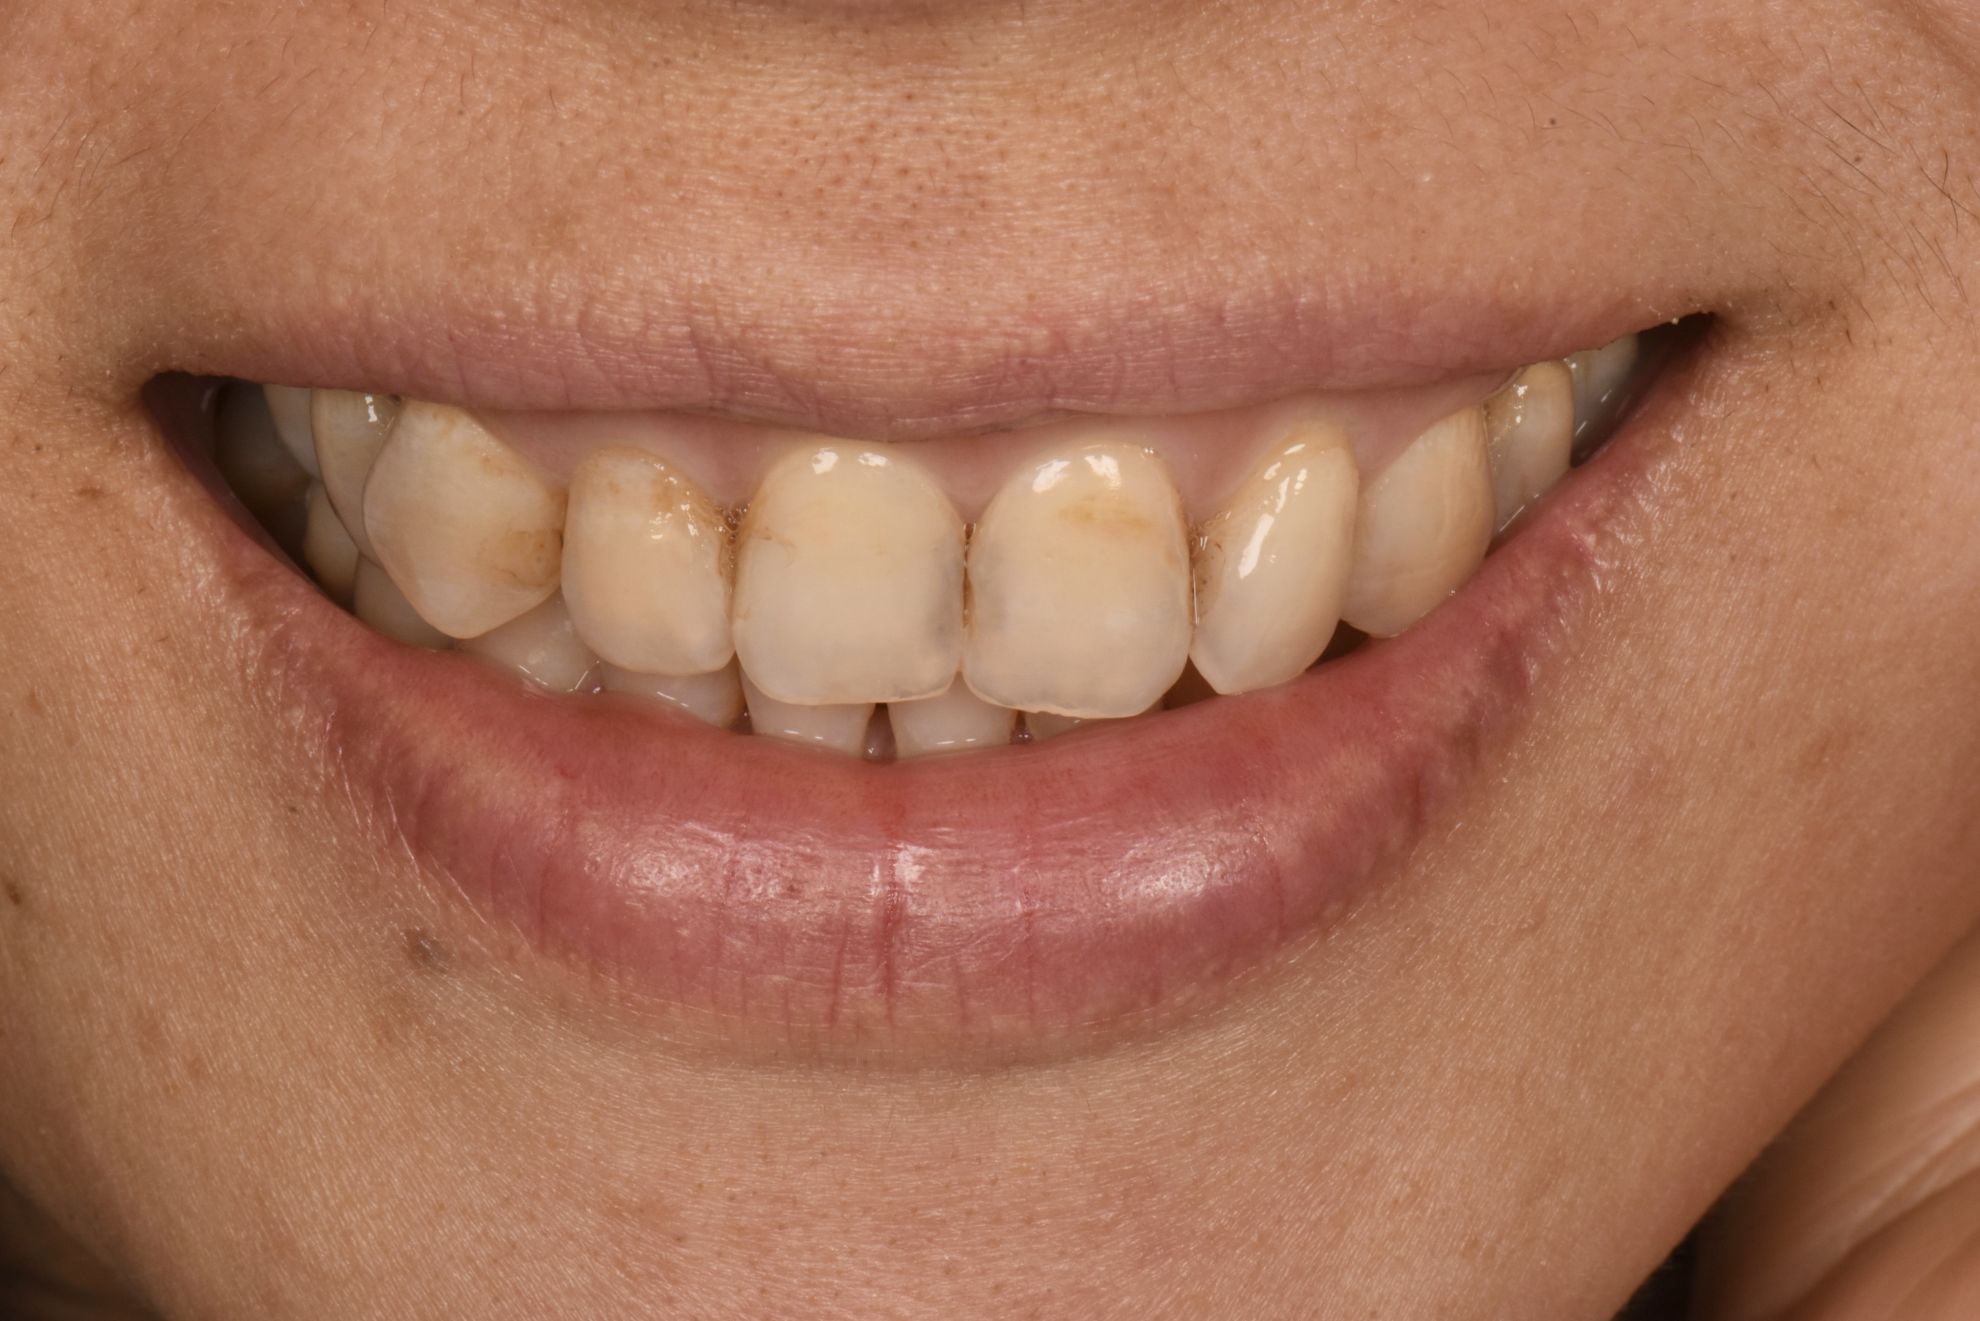

X小姐因嚴重蛀牙,時不時感到牙齒隱隱作痛,而牙齒表面也因為這樣看起來不健康也不美觀。

經過陳醫師細心的臨床診斷後,先進行了『根管治療』,再製作了『玻璃纖維牙柱心』和

3M Lava全瓷冠』以得到最大強度的修復,3M Lava全瓷冠,細心修復每顆牙齒的結構性和密合度外,更大幅改善了前牙美觀問題,提升病患個人於社交上乾淨健康的牙齒形象。

治療前